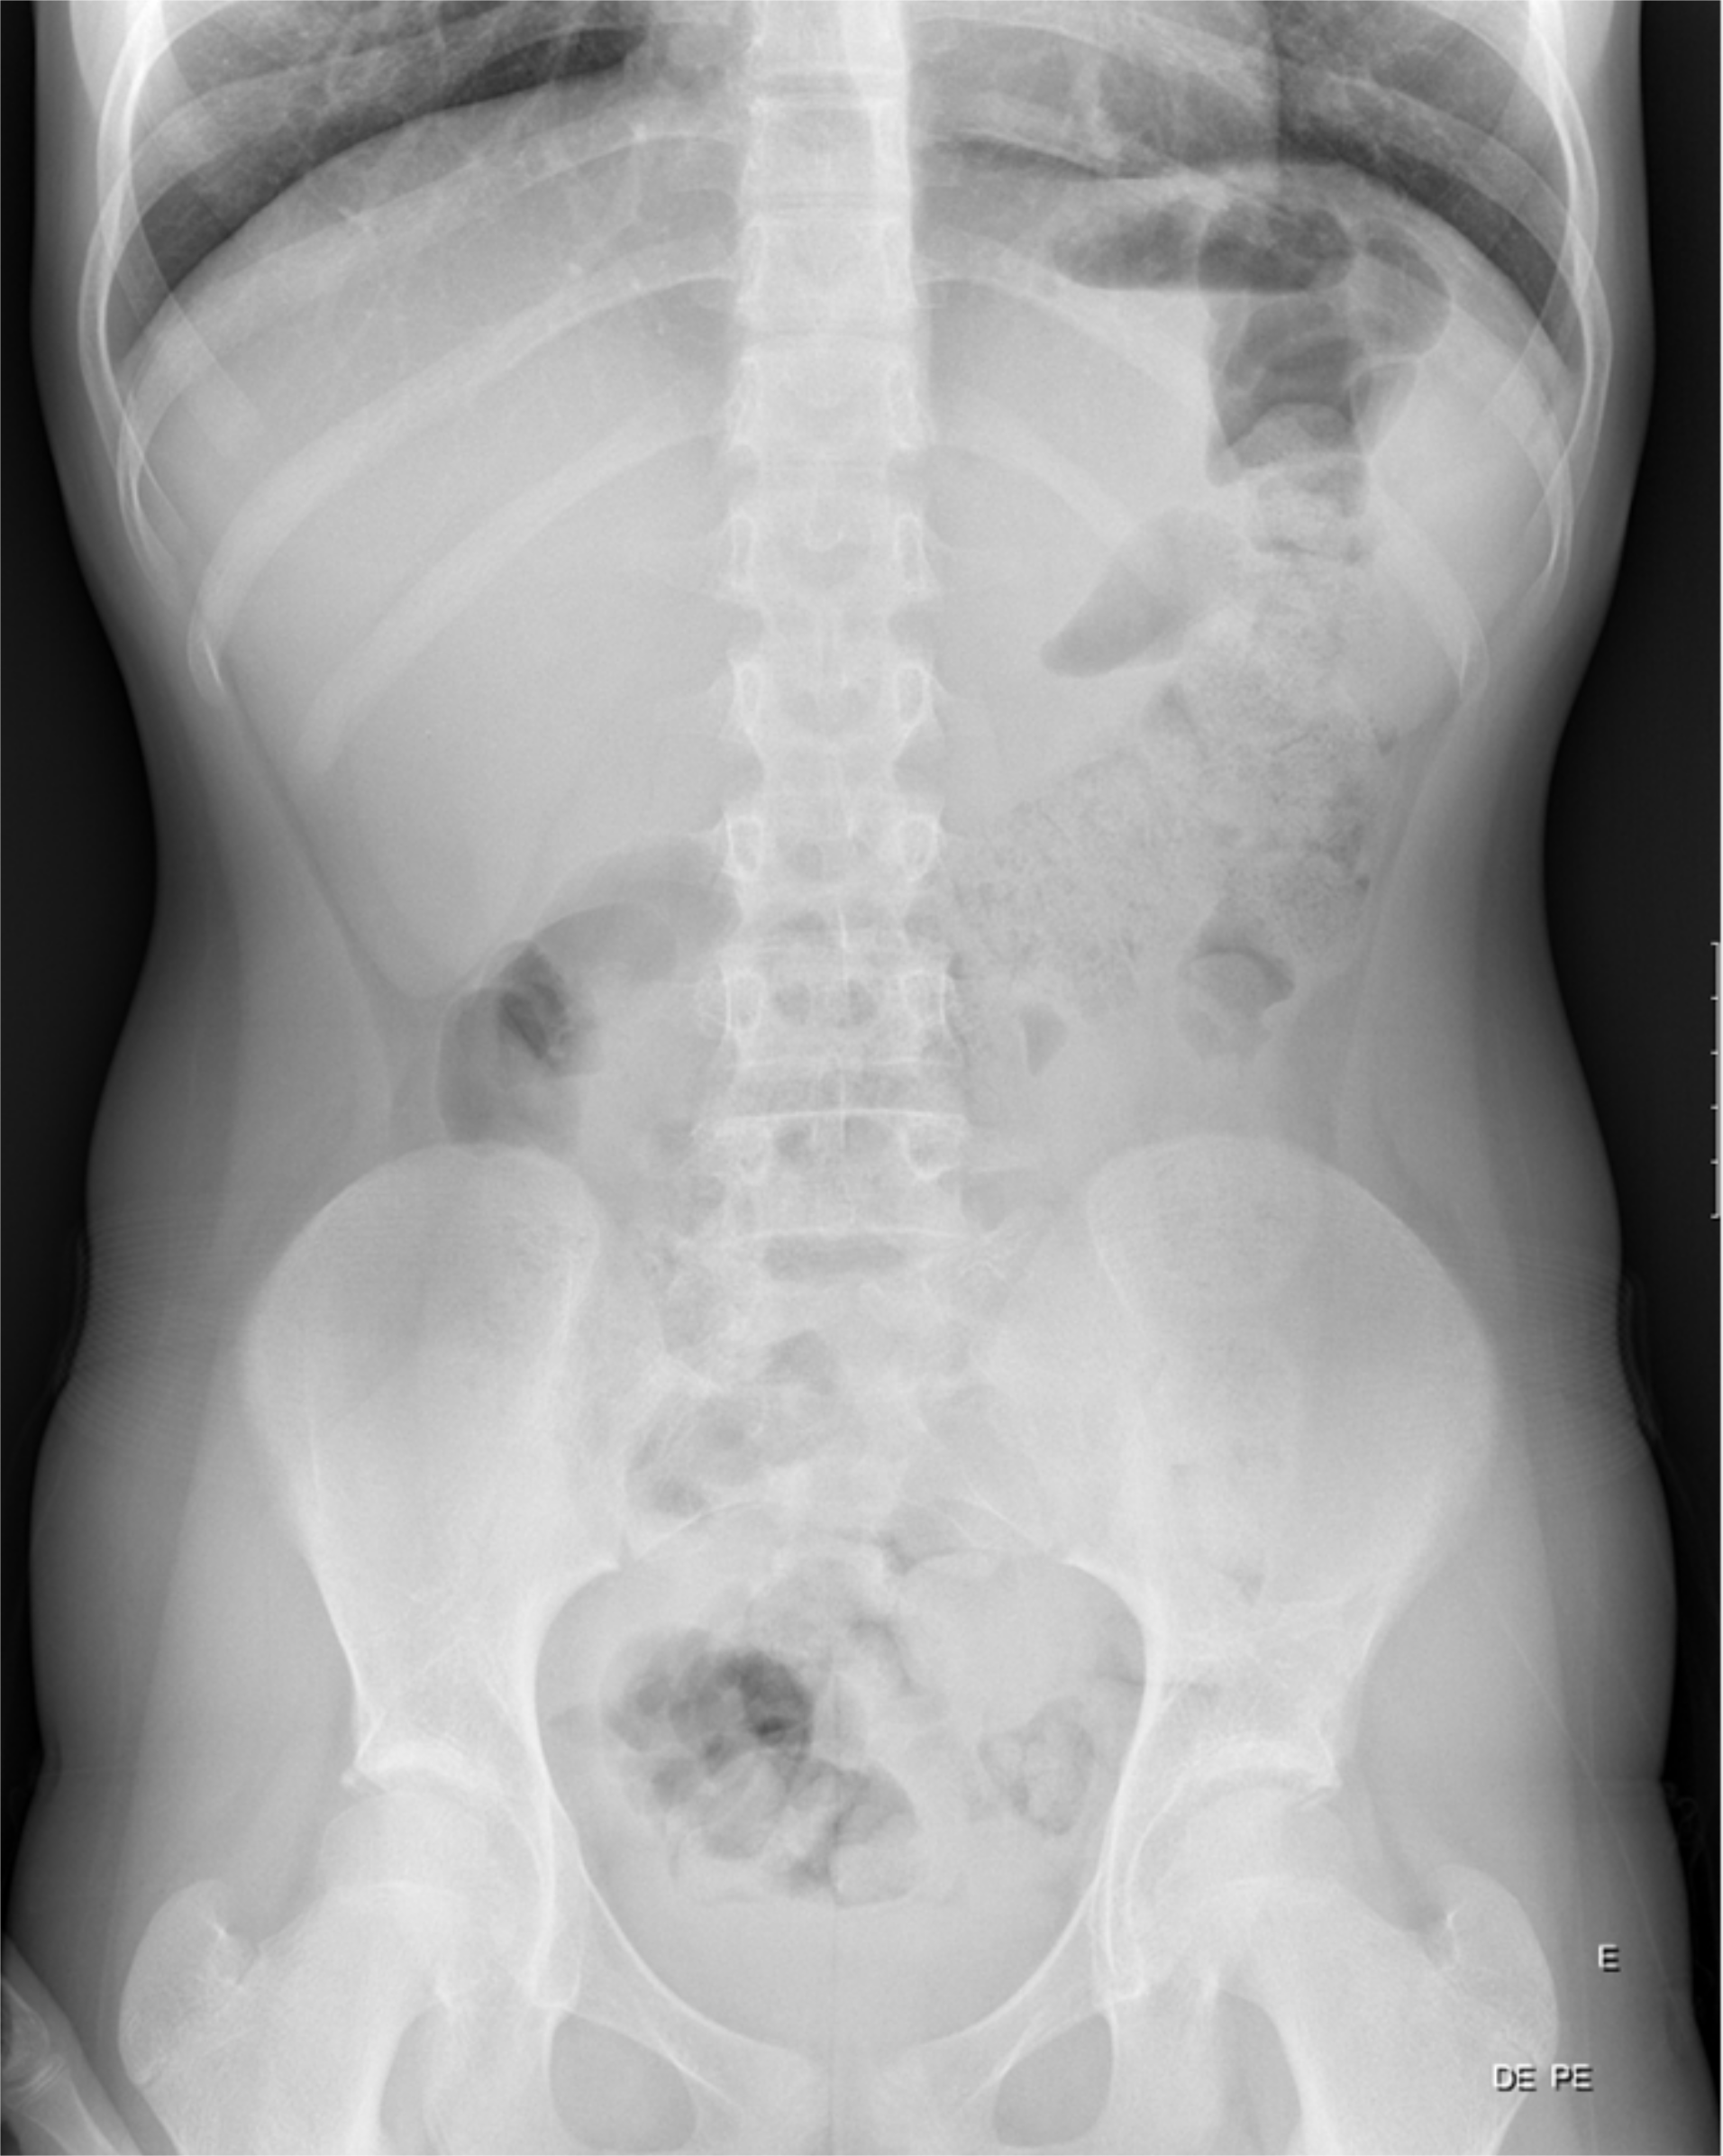

Duodenal hematoma is a rare complication of endoscopic duodenal biopsy, with just a few cases reported in children in the literature available.

The authors present a case of a 13 year-old girl, with a history of Noonan Syndrome and neurofibromatosis type 1, who presented abdominal pain and vomiting after an endoscopic duodenal biopsy.

In this article, we describe the clinical case, imaging findings, evolution and therapeutic approach.